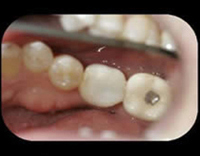

The Patient wears a "healing cap" while the implant integrates with the bone. Typically three to six months.